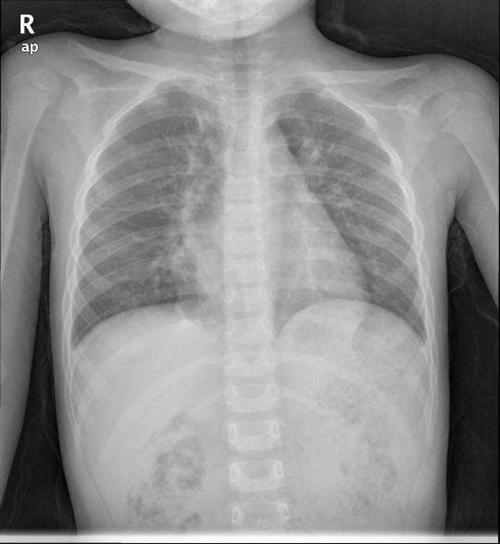

发病机制1.真性膜部瘤 室间隔膜部纤维组织明显增生,形成囊袋样瘤状物突向右心室、三尖瓣隔瓣后、隔前瓣交界处,甚至经三尖瓣口突向右心房。囊袋顶部常伴穿孔。室缺周边由膜部组织及纤维结缔组织构成(图1A,B)。

相关图片